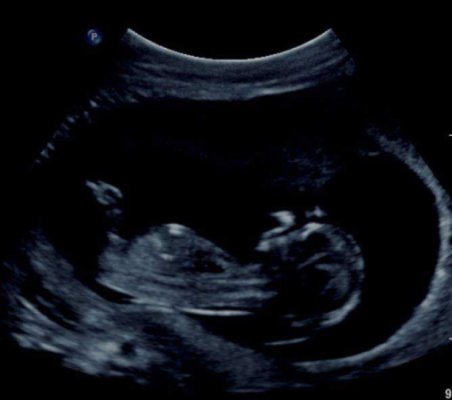

I posted this on the strictly nub theory page on fb and the moderator guessed boy. I was so desperate for a girl. Does it look like a boy nub? This is my last baby so I need to start getting my head around it now I think. Scan was at 13weeks (baby measured 12weeks 6 days at this scan).

Thanks Attachment 41811Attachment 41812